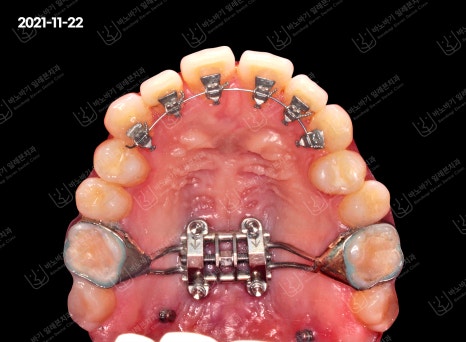

상악은 우선 악궁확장을 통해 좁은 배열을 좌우로 넓혀주고 설측방식으로 앞니를 정리해서 가지런하게 만들어주었습니다.

교정이 진행 중인 사진

환자분께서는 설측방식 덕분에 교정할 때 장치가 보이지 않아 어디서든 자신 있게 웃는다며 만족스럽다고 말씀하셨습니다.

물론 이렇게 브라켓을 안쪽에 부착하고 와이어를 연결하면 중간점검이 까다로워지는 만큼, 난이도가 높다고 볼 수 있어요.